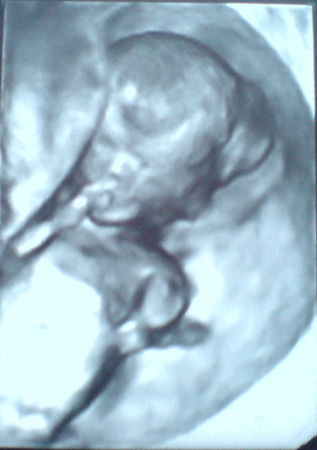

12 недель УЗИ